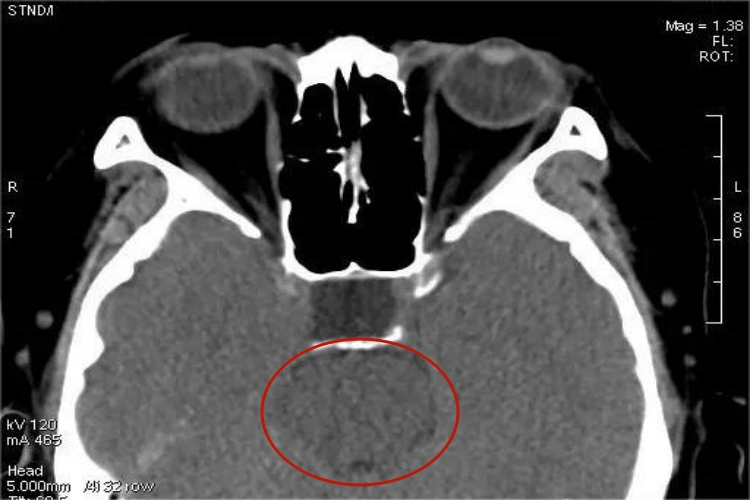

空泡蝶鞍,又称为空泡蝶鞍综合征,是脑部影像学检查的一种结果,具体指的是蝶鞍部位(即颅底部)存在异常的蛛网膜结构。这个囊肿会压迫正常的垂体结构,引起垂体功能的异常改变,可以从成因、症状、分类等方面进行了解。

- 原发性空泡蝶鞍综合征:没有明显病因可寻,可能与先天因素或脑脊液循环障碍有关。

- 继发性空泡蝶鞍综合征:发生在鞍内或鞍旁手术、放射治疗后,由于手术或放疗导致的鞍区结构改变。